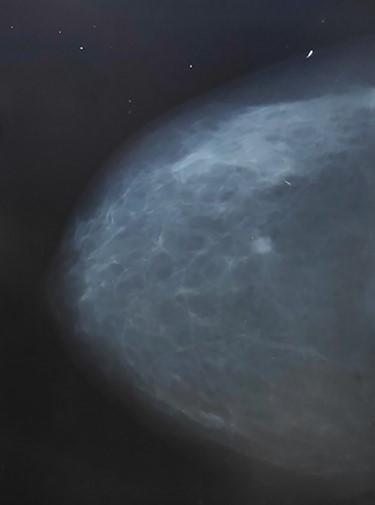

A 59-year-old female patient presented to our outpatient clinic with a palpable mass in her left breast. The patient had no family history of neither breast cancer, endometrial nor ovarian cancer and no comorbidities except for hypertension which was controlled. On examination the mass was suspicious and hard inconsistency; a mammogram was done, and it revealed a BIRADS (4) breast mass 13.5 × 8.5 mm at 3 o’clock position (Fig. 1).

Mammogram shows braids 4 suspicious mass at left upper quadrant (lt breast).